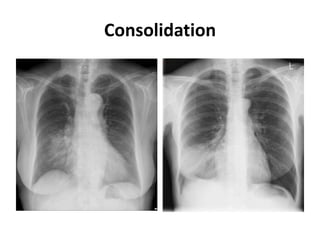

Consolidation